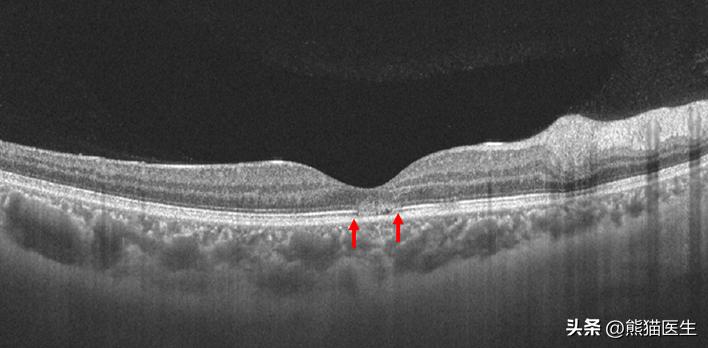

检查发现,本来只是100度轻度近视的谢女士,左右眼视力分别下降到0.02和0.1,而根据WHO的标准,视力低于0.05就可以定义为盲。通过OCT以及眼底血管造影进一步检查,李杰医生发现谢女士黄斑区视网膜外层存在异常的高反射信号,这代表着局部可能存在炎症或者缺血改变。经过综合诊断,李女士的眼部疾病确诊为急性黄斑神经视网膜病变(AMN),属于一种眼科罕见病。

红色箭头处标记为病灶